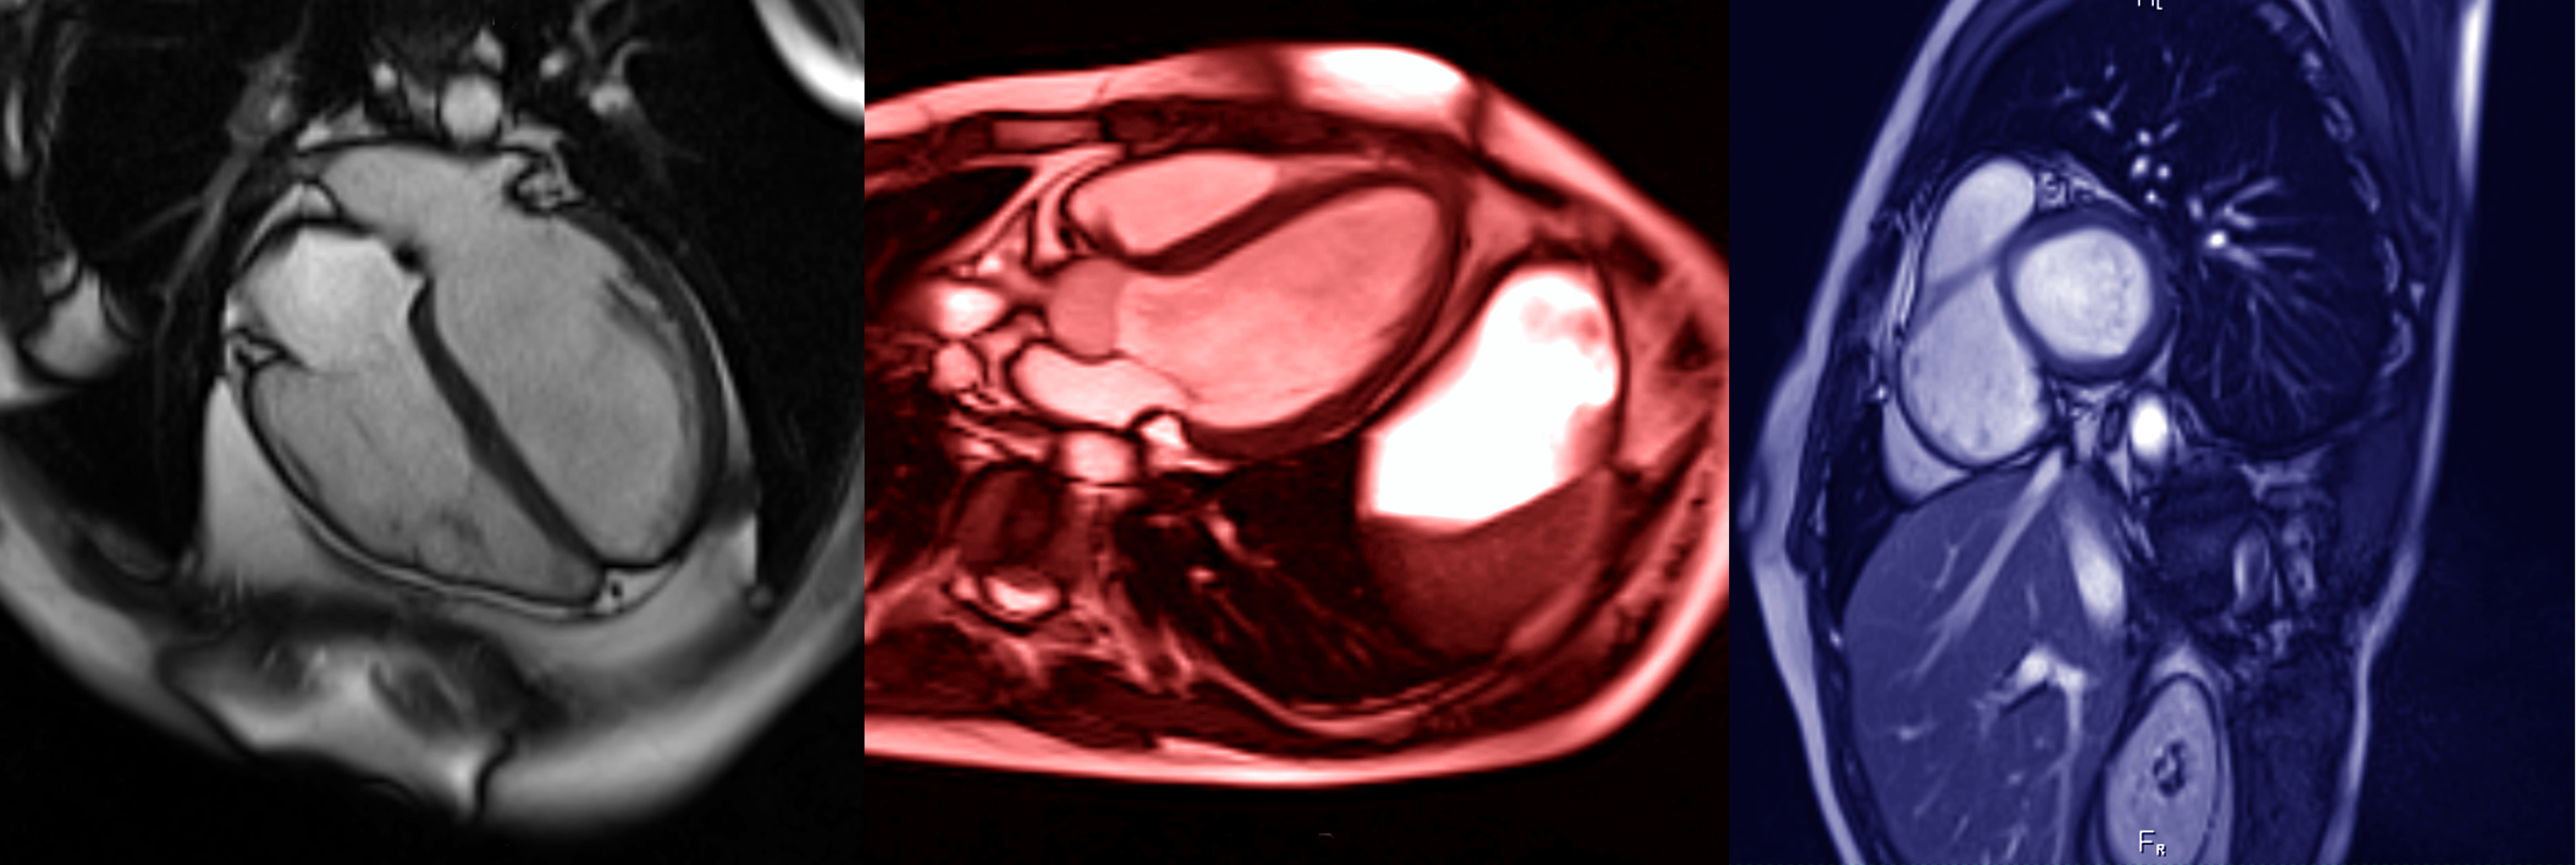

L'imagerie cardiovasculaire est une sous-spécialité de la radiologie qui permet de

visualiser l'état circulatoire de l'appareil cardio-vasculaire à des fins diagnostiques,

thérapeutiques ou de recherche. Elle permet d’analyser votre cœur et l'anatomie

environnante.

Les examens comprennent les radiographies, l’échographie, l’IRM et le scanner.